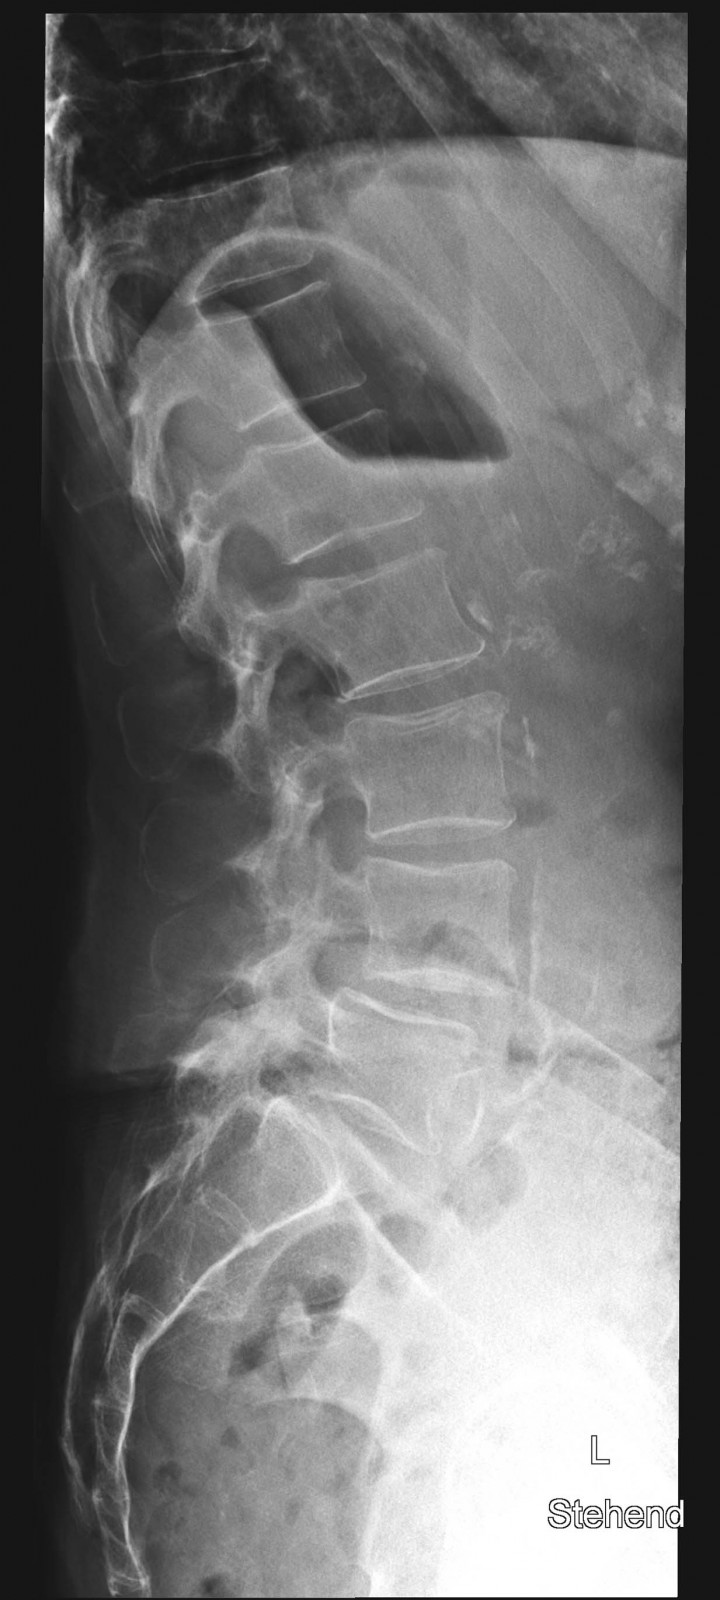

80 jährige Patientin mit chronischen linksbetonten Schmerzen lumbal am Übergang zum Becken

WS seitlich